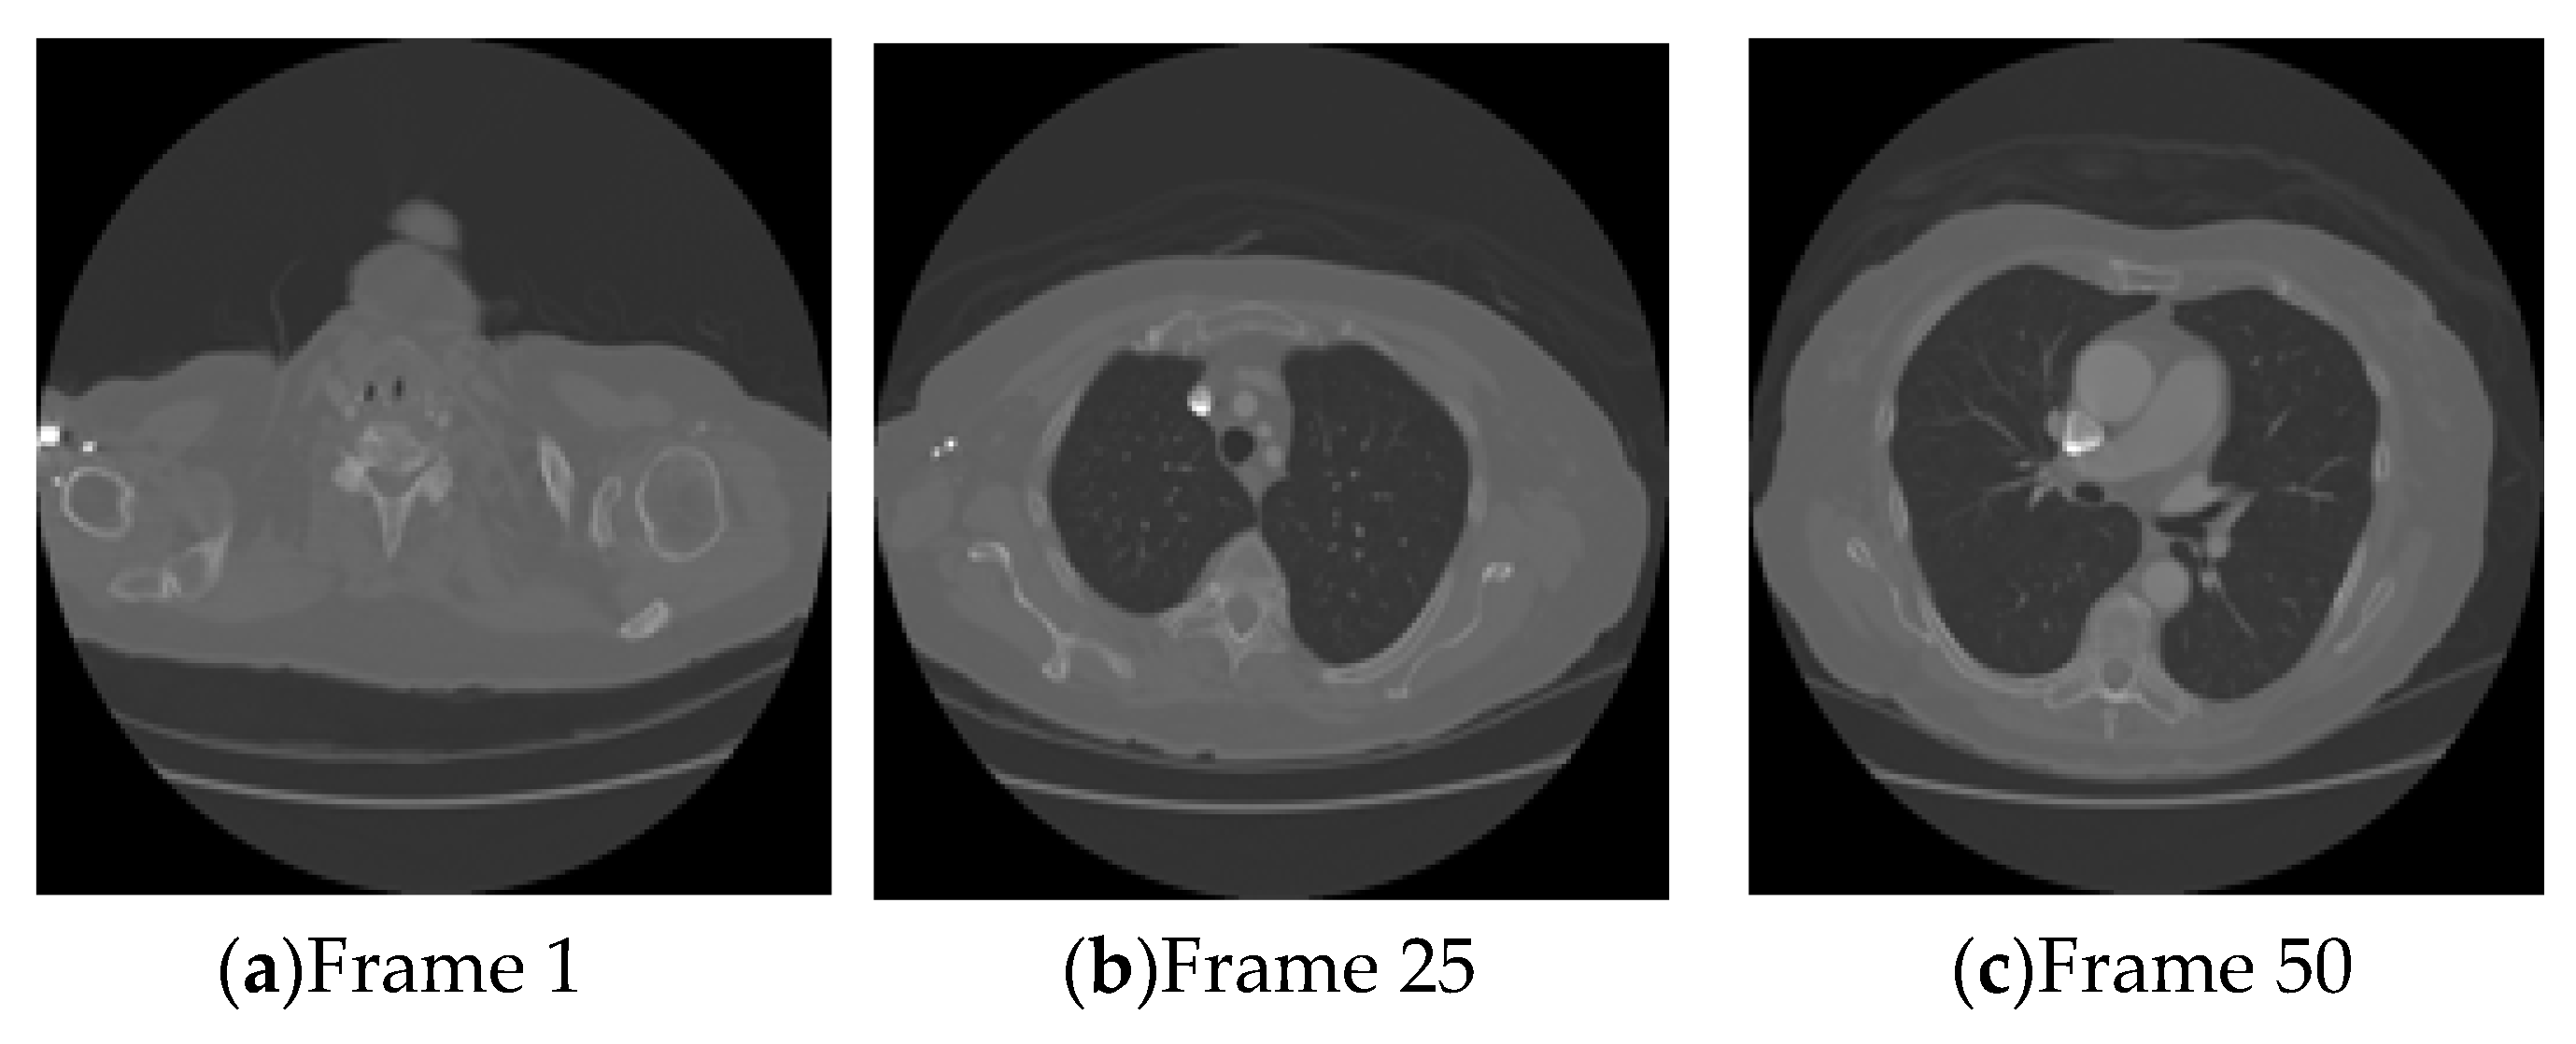

Figure 10 shows a few frames from ‘Lung’ DICOM image database. Figure 11a shows a watermarked frame after non-fading based collusion operation. Figure 11b–f show watermarked DICOM frames after time-varying collusion attacks with different SNR (transmitting each watermarked DICOM frames through fading channel at different SNR values) and then averaged. Table 5 shows the BER (bit error rate) values for different watermarks extracted from the colluded average images. Low BER values indicate that the scheme is robust to fading like collusion operation. It is also seen that the BER values for columns 2–5 are quite low compared to the BER values in column 6. The low values of BER clearly indicate that the parties having watermarks, i.e., W1, W2, W3, W4, are identified as colluders. It is also quite clear from the numerical values of BER that parties involved in collusion operation would unambiguously be identified from the innocent users (W5). Similar results are also obtained if different combinations of watermarked images in the set are used in collusion operations. Table 6 shows the average results for non-fading based collusion operation. High NCC values in Table 6 indicate that the scheme is also robust to non-fading based collusion operation. Table 7 shows the average value of the colluder identification performance of the proposed scheme.

Figure 10. Lung DICOM image database.